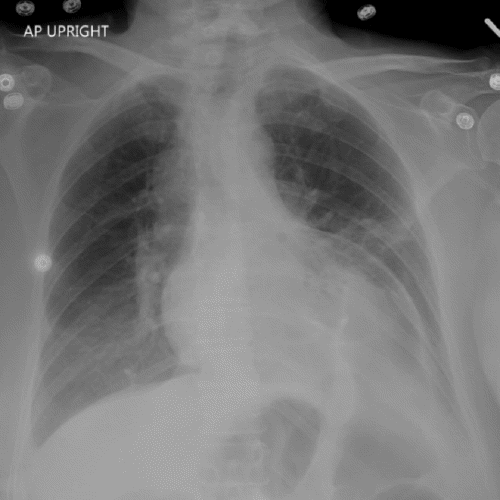

By hospital day 4, the patient was transferred to the floor. She had difficulty with the return of bowel function, but otherwise, she was doing well, working with physical therapy. On hospital day 8, she developed mild leukocytosis and tachycardia, prompting a chest X ray. This exam revealed a new, large diaphragmatic hernia, concerning for a traumatic hernia at the anterior diaphragm (Figure 1A). A review of a previous chest X ray confirmed that this was a new finding (Figure 1B). Aside from tachycardia, her vital signs were stable, and she was breathing comfortably on 2 L/min of oxygen. She denied new complaints at the time of the exam.

Figure 1. Diagnostic and Prior Chest X Rays. Published with Permission

A) Large hernia from left anterior diaphragm, concerning for traumatic hernia

B) Review of chest X ray from five days earlier demonstrated normal findings